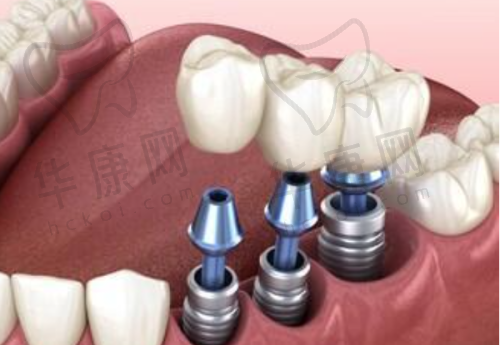

该口腔门诊部主打德系种植技术,在瑞士ITI种植牙方面有着独特的优势。其擅长即刻种植和微创种植技术。即刻种植技术可以在拔牙后立即进行种植,大大缩短了患者的治疗周期,减少了多次就诊的麻烦。而微创种植则是通过微小的切口进行种植手术,对患者的创伤小,术后修复快,患者在术后的疼痛感也相对较轻。比如,曾经有一位患者在溧水瑞齿固德口腔进行瑞士ITI种植牙,采用微创种植技术,术后当天就能正常饮食,修复速度超出了患者的预期。

医院拥有新型的设备,为瑞士ITI种植牙手术提供了精细的保护。精良的口腔CT设备可以清晰地显示患者口腔内部的结构,帮助医生更正确地了解患者的牙槽骨情况,从而制定出更合适的种植方案。在手术过程中,使用的种植器械也都是经过严格筛选的,确保手术的安心性和成功几率。例如,通过精良的设备,医生可以严谨地控制种植体的植入位置和角度,提高种植牙的稳定性和美观度。